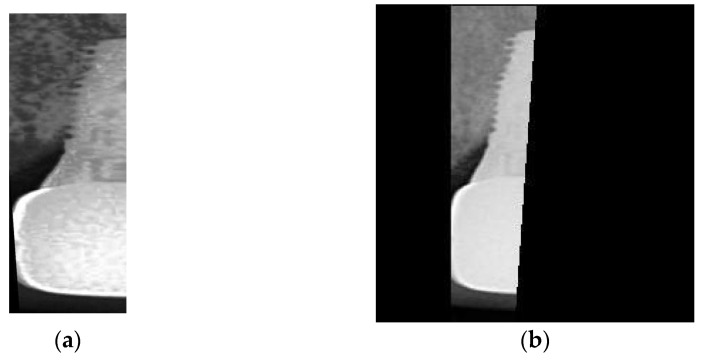

The key issue in this step is to determine the Region of Interest (ROI) for training the object detection model. If the ROI encompasses the entire implant, the damage feature of the screw thread may not be classified accurately. This is because the area above the screw thread occupies most of the picture as depicted in Figure 2a, which can also make subsequent cropping steps challenging. Labeling only the screw thread, on the other hand, will not affect the determination process. Hence, the research sets the ROI to the thread instead of the implant body as shown in Figure 2b, to preserve the damage features of the screw thread as much as possible. Additionally, the damage detection also requires the gingival features surrounding the screw thread. Therefore, in the subsequent step of cropping the screw thread, the ROI returns the position that expands horizontally by several pixels to preserve these features for the next step.

Figure 2.

Illustrating the marking of the Region of Interest (ROI) in this study. (a) The dental implant is depicted, including the area above the screw thread. (b) Only dental implants with screw threads are included in the ROI.